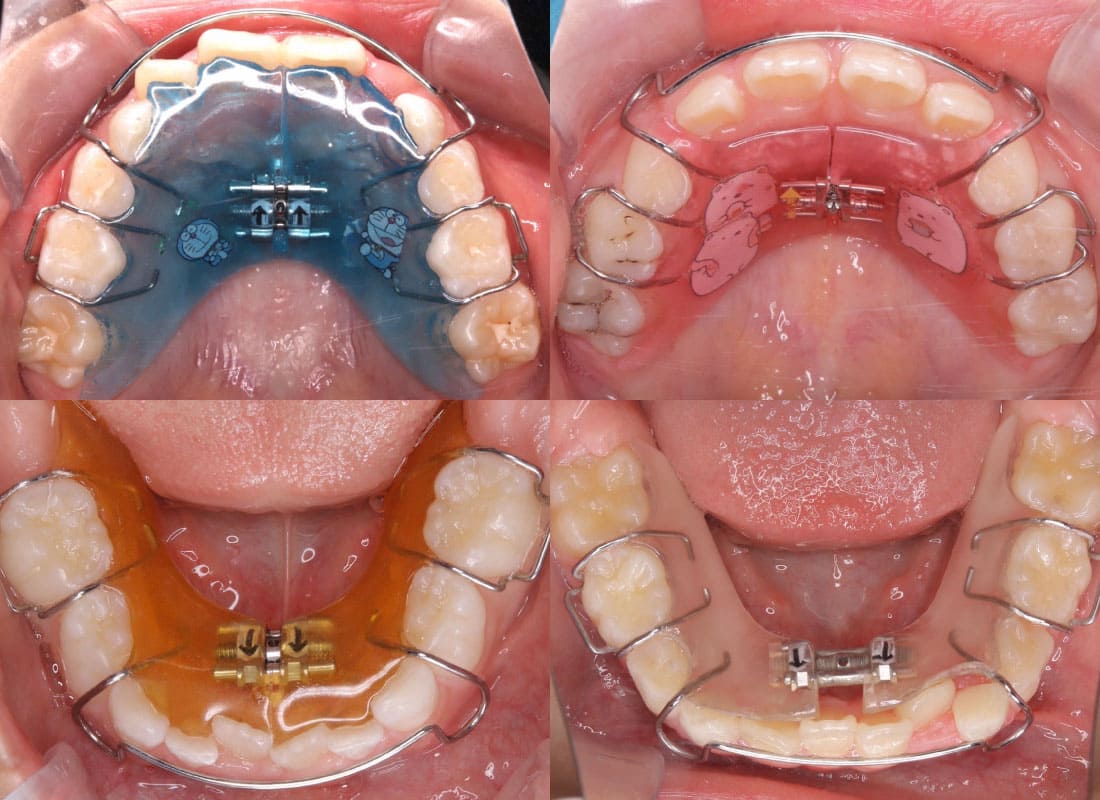

1期治療で使用する装置

拡大床

- 機能

- 横に広げるための装置

- 期間

- 6か月~10か月程度

成長期のお子さまの顎をゆっくりと広げる矯正装置です。顎の成長を正しい方向へ導くことで、歯がきれいに並ぶための土台を整えます。歯を無理に動かすのではなく、顎の成長を活かした治療のため、痛みが少なく、お子さまへの負担が比較的軽いのが特徴です。

拡大床は、多くの場合1期治療の中心となる装置で、将来的な本格矯正の必要性を減らすことにもつながります。 -